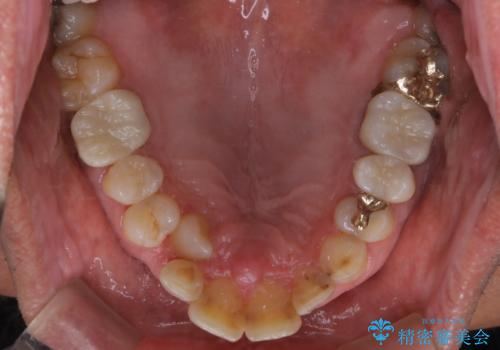

歯科衛生士による専門的なクリーニングPMTC(保険外治療)60分コースを行いました。

専門的な機械・材料を使用して徹底的に汚れを取り除きました。

染め出しをして、磨き残しの確認・ブラッシング指導も行いました。